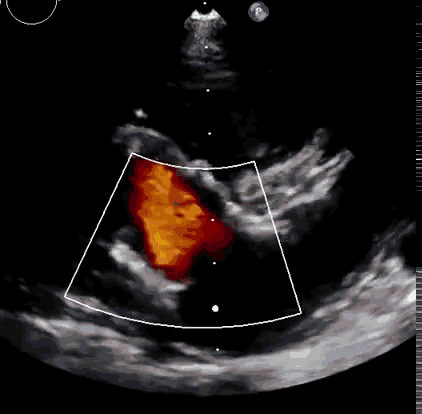

上海中山醫(yī)院葛均波院士、錢菊英院長(zhǎng)、周達(dá)新教授、潘文志教授、潘翠珍教授、李偉教授共同完成此次臨床前研究。術(shù)后葛均波院士對(duì)Lux-Valve Plus的器械操作性能給予了高度評(píng)價(jià),DSA和超聲影像也顯示出在本次研究中Lux-Valve Plus的安全性和有效性俱佳。

本次臨床前研究經(jīng)右側(cè)頸靜脈置入LuX-Valve Plus輸送系統(tǒng)可調(diào)彎鞘管,在DSA及超聲引導(dǎo)下將人工三尖瓣瓣膜植入到原有三尖瓣位置,利用獨(dú)特的錨定技術(shù)將人工瓣膜支架可靠固定在預(yù)定的位置。